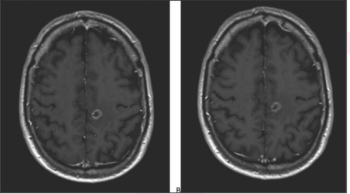

Nonsuppressed background parenchymal enhancement could indicate patients who will show inferior response and allow for a personalized redirection of treatment.

The algorithm is the first step towards developing an artificial intelligence-augmented radiology workflow that can support image interpretation to improve diagnosis and prognosis.